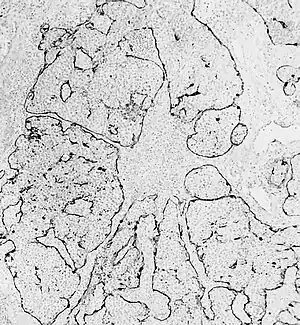

Pathophysiology

Esthesioneuroblastoma is of neurocrest origin, arising from olfactory sensory cells in the olfactory epithelium.[1] The olfactory epithelium consists of olfactory sensory cells, sustentacular cells and basal cells.[1] Esthesioneuroblastoma consists of lobular sheets with neurofibrullar fibers and rosettes.[4] Hyam's classifications are an important way of determining prognosis.[10]